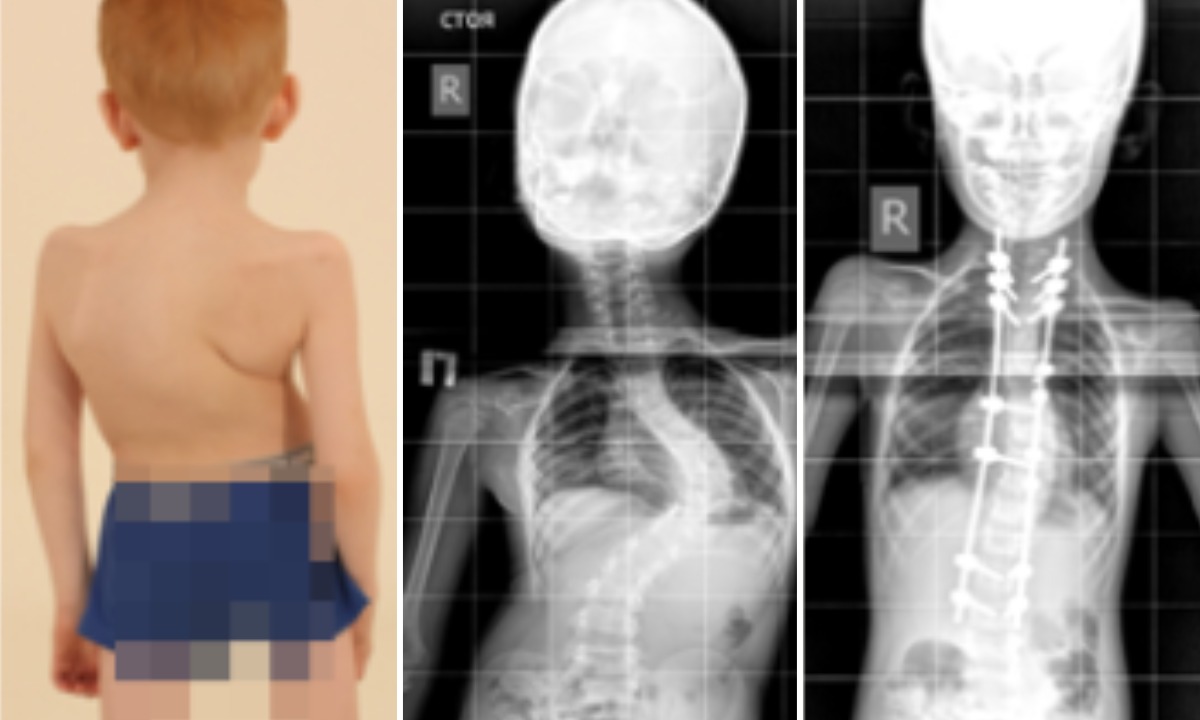

Наследственная болезнь Элерса-Данло, от которой у ребенка в полтора года деформировался позвоночник — дефект в синтезе коллагена, из-за этого у пациентов возникает повышенная растяжимость соединительной ткани, гипермобильность суставов и другое, рассказали в Центре Илизарова. Здесь впервые прооперировали мальчика в 2019 году.

— Лечение проводилось в два этапа. Первоначально мальчику провели подготовительный этап — коррекцию с помощью гало-тракции – метода скелетного вытяжения за кости черепа. Вторым основным этапом выполнили коррекцию сколиотической деформации с помощью погружной металлоконструкции, — рассказала к.м.н., вертебролог Центра Илизарова Полина Очирова.